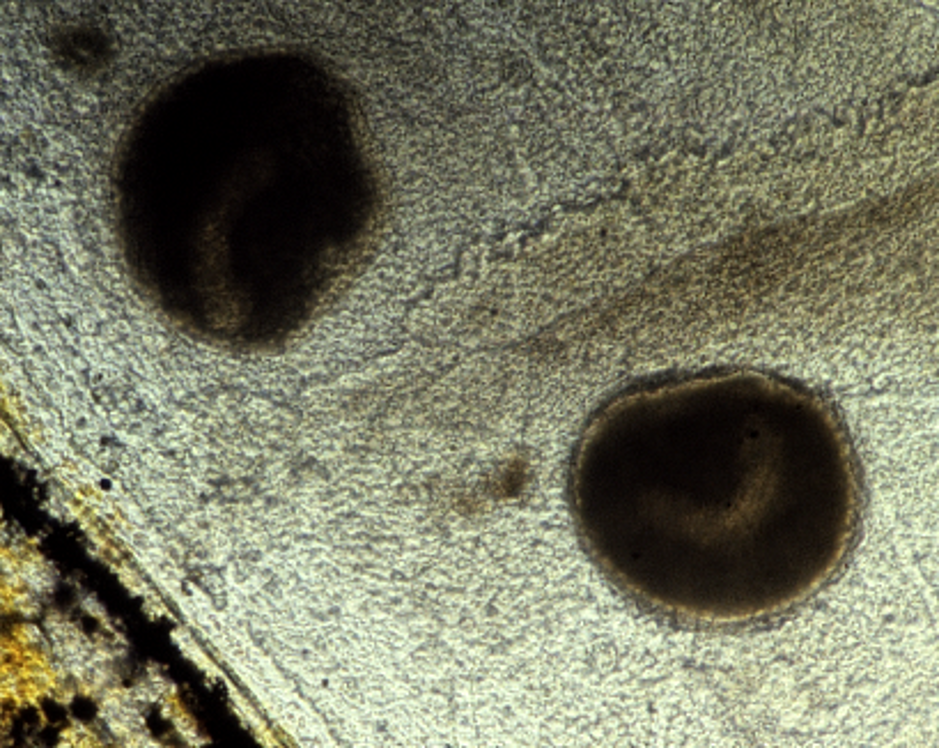

영양체는 어류의 피부, 지느러미, 아가미 상피에 기생하며 숙주 세포와 세포 잔해를 섭취하는 섭식 단계이다.[4] 이 단계에서 온도에 따라 기생충은 짧은 시간에 빠르게 성장할 수 있다. 육안으로 관찰 가능한 흰색 반점으로 나타나며, 크기는 0.3~1mm 정도이다. 영양체가 이 크기에 도달하면 숙주 표피에서 벗어나 섬모로 덮여 있는 톰몬트가 되어 자유롭게 헤엄친다.[4]2. 2. 톰몬트 (Tomont)

세포분열자 침투는 물고기 표면의 자극을 반영하는 불규칙한 헤엄과 움직임을 유발할 수 있다. 영양체는 물고기를 먹고 직경이 약 0.3mm에서 0.5mm까지 자랄 때까지 육안으로 보이지 않는다. 흰 반점은 직경이 1mm 이상에 달할 수 있으며 피부와 지느러미에서 쉽게 식별할 수 있지만, 아가미에 부착된 영양체는 아가미 덮개(새개) 때문에 보기가 어렵다.[3][10]

Ich 감염은 일반적으로 물고기의 몸이나 지느러미에 하나 또는 여러 개의 특징적인 흰 반점으로 나타난다. 흰 반점은 숙주 세포(표피 세포 및 부위로 유인된 백혈구)를 먹고 직경이 1mm까지 자랄 수 있는 영양체이다.[3][10] 영양체가 탈출한 후 병변이 있는 심한 감염은 피부를 불규칙하고 솜털 모양이며 회색으로 만든다. 아가미 감염은 수면에서 호흡을 유발하고 새개의 환기 운동을 증가시킬 수 있다.

피부나 지느러미에 보이는 흰색 반점(트로폰트)은 *I. multifiliis* 감염의 잠정적인 진단 근거가 된다. 피부 및 아가미 도말 검사를 통해 확진할 수 있는데, 피부, 지느러미 또는 아가미 표면을 긁어내어(커버 슬립 또는 메스 사용) 커버 슬립 아래에 물 몇 방울을 떨어뜨린 후 현미경 슬라이드에 장착하여 광학 현미경으로 관찰한다(20-400 배율). 트로폰트는 천천히 회전하며, 빠르게 움직이는 섬모로 덮여 있고, 뚜렷한 말굽 모양의 대핵을 가지고 있어 현미경 검사로 확인할 수 있다.[13] 분자 진단은 기생충의 i-항원을 코딩하는 유전자를 기반으로 하며, PCR 및 정량적 실시간 PCR로 수행된다.